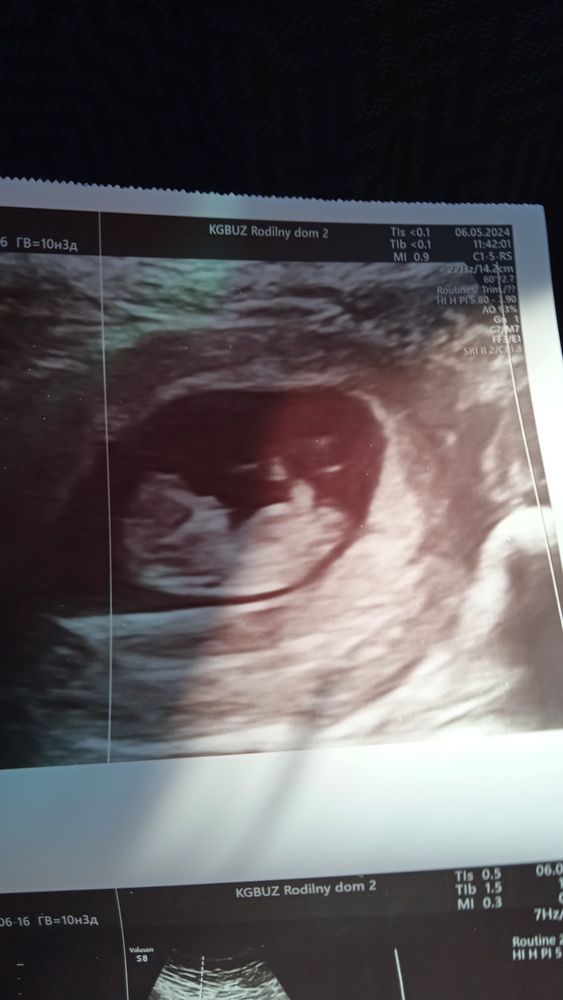

Мы растем...

06.05.2024

Размеры плода Пол ребенка !!!!!